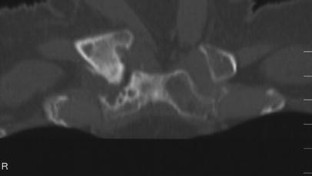

The SAPHO syndrome was a term coined to include a variety of musculoskeletal disorders associated with skin conditions, mainly palmoplantar pustulosis and acne conglobata. It is more correctly a spectrum which includes the following: skin lesions, osteoarticular manifestations of synovitis hyperostosis and osteitis affecting particular target sites, and·a clinical course marked by relapses and remissions. The major sites of involvement are the anterior chest wall, the spine, long bones, flat bones, and large and small joints. The distribution and severity of involvement varies from the adult to the pediatric form of chronic recurrent multifocal osteomyelitis (CRMO). The diagnosis of SAPHO syndrome is not difficult when the typical osteoarticular lesions are located in characteristic target sites. The diagnosis is more difficult if atypical sites are involved and there is no skin disease.